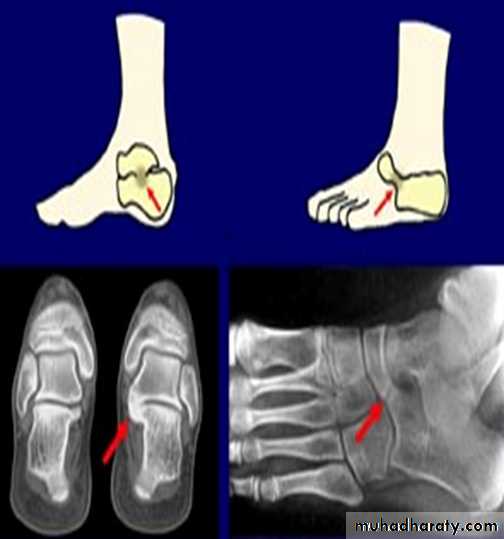

This is a condition that occurs in adolescents where the foot at rest looks normal but after walking or exercise it get painful with spasm of the peroneal muscles so the foot go into valgus and get flattened.Sometimes its idiopathic although tarsal fusion (coalition) by a bony or cartilage bar has been commonly blamed.

X-ray, CT scan or MRI may show the abnormal coalition.